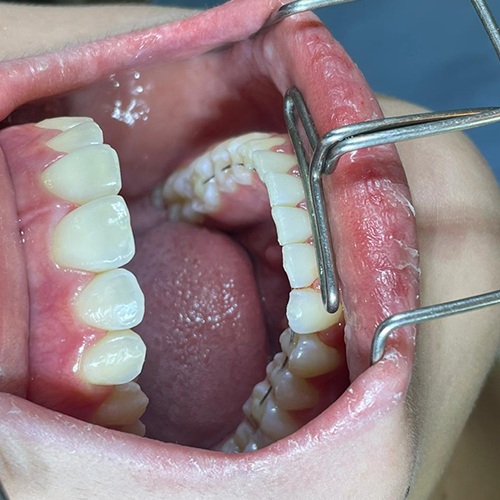

Profundice en la técnica del Hilo Invisible BOT con clases teóricas y casos reales — un procedimiento que ofrece estética, comodidad y resultados al paciente.

Comprueba en la práctica cómo el conocimiento se transforma en resultados reales a través de los casos de nuestros alumnos.

SALA DE PROCEDIMIENTOS

Siga clases prácticas y la evolución de casos clínicos reales directamente desde la clínica del Dr. Ary Nunes.